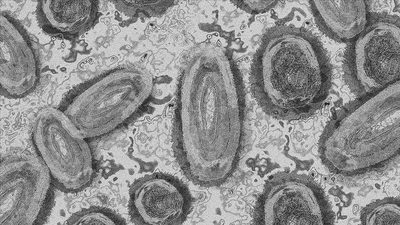

Afrika'ya özgü bir hastalıkken Dünya Sağlık Örgütü (DSÖ) tarafından 2 haziran 2022' de Amerika ve Avrupa başta olmak üzere tüm dünyada 780 maymun çiçeği vakası bildirilirken, son bir kaç gün önce DSÖ tarafından yayınlanan raporda vaka sayısının 4 bin 300'e ulaştığı bildirildi ve dünya sağlık gündeminin ilk sıralarında yerini aldı. Sağlık Bakanlığımızca da ülkemizde 1 maymun çiçeği vakasının tespit ve izole edildiği bildirildi.

DSÖ tarafından bildirilen vakalarda, endemik olmayan ülkelerde bu hastalığa bağlı ölüm vakası henüz bildirilmedi. Ancak endemik olarak görülen Afrika ülkelerinde bu hastalığa bağlı ölüm oranı yüzde 1-10 arasında devam ediyor. Oysa çiçek hastalığında ölüm yüzde 30 civarında olmuştur ve çiçek hastalığına kıyasla daha az bulaşıcıdır. Dünyada ilk vakaya 1970 yılında Afrika'da Kongo Cumhuriyeti'nde rastlandı. 2022 yılına kadar Avrupa'da insandan insana bulaş hiç raporlanmadı.

Bilimsel indeksin bir göstergesi olan impact faktörü yüksek bulunan Lancet dergisi yayınladığı son raporunda, son aylarda gündeme oturan maymun çiçeği virüs hastalığıyla ilgili çarpıcı detaylarda bulundu. Vakaların çoğu erkek ve ortalama yaş 41 di. Vakaların yaklaşık yüzde 18' inde hiçbir belirti olmaması dikkat çekiciydi. Yorgunluk ve ateşin en çok görülen belirtiler olduğu ortaya konuldu. Yine bu vakaların (ikisi dışında) bilinen bir vaka ile temas etmedikleri ve Afrika'yı ziyaret etmedikleri anlaşıldı. Döküntülerin genellikle genital bölgede görüldüğü rapor edildi.